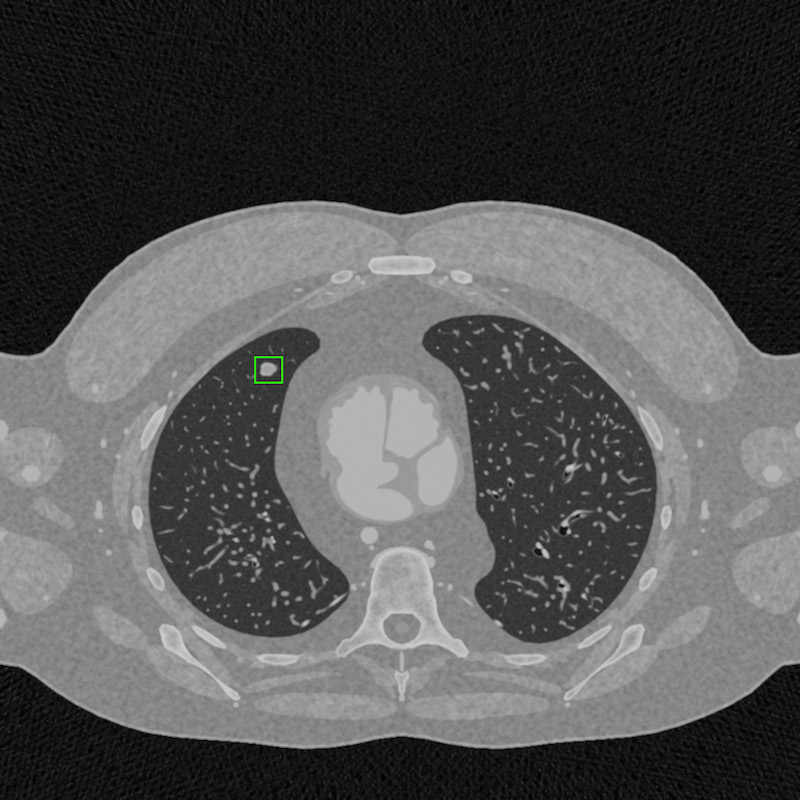

Ook medische toepassingen beginnen de eerste resultaten op te leveren. Algoritmiek kan bijvoorbeeld gebruikt worden om knobbeltjes in longen te classificeren als goed- of kwaadaardig. Met synthetische data kunnen we een CT-scan nabootsen op iedere variant van longen en knobbeltjes die denkbaar is. Je wilt immers zeker weten dat een dergelijk algoritme het altijd goed doet en het scheelt ook nog allerlei privacygerelateerde problemen.